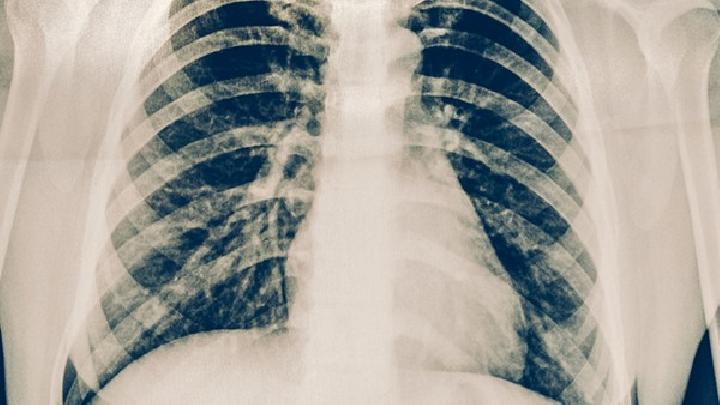

肺结核这种疾病是结核病的一种,其实结核病是由结核分枝杆菌引起的慢性传染病,可侵及许多脏器,以肺部结核感染最为常见,所以叫肺结核,肺结核的传染源主要是排菌者,那么得了肺结核的的患者怎么办,肺结核什么时候好,下面我们就来了解一下。

那么肺结核患者什么时间能好呢。其实这就得看肺结核患者的患病轻重程度了。肺部体征依病情轻重、病变范围不同而有差异,早期、小范围的结核不易查到阳性体征,病变范围较广者叩诊呈浊音,语颤增强,肺泡呼吸音低和湿啰音晚期结核形成纤维化,局部收缩使胸膜塌陷和纵隔移位。在结核性胸膜炎者早期有胸膜摩擦音,形成大量胸腔积液时,胸壁饱满,叩诊浊实,语颤和呼吸音减低或消失。